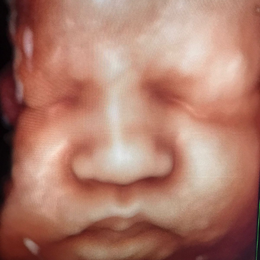

Ecografía del corazón fetal en 4D

- Las formas nuevas de ecografía pueden proporcionar imágenes en 5-D.